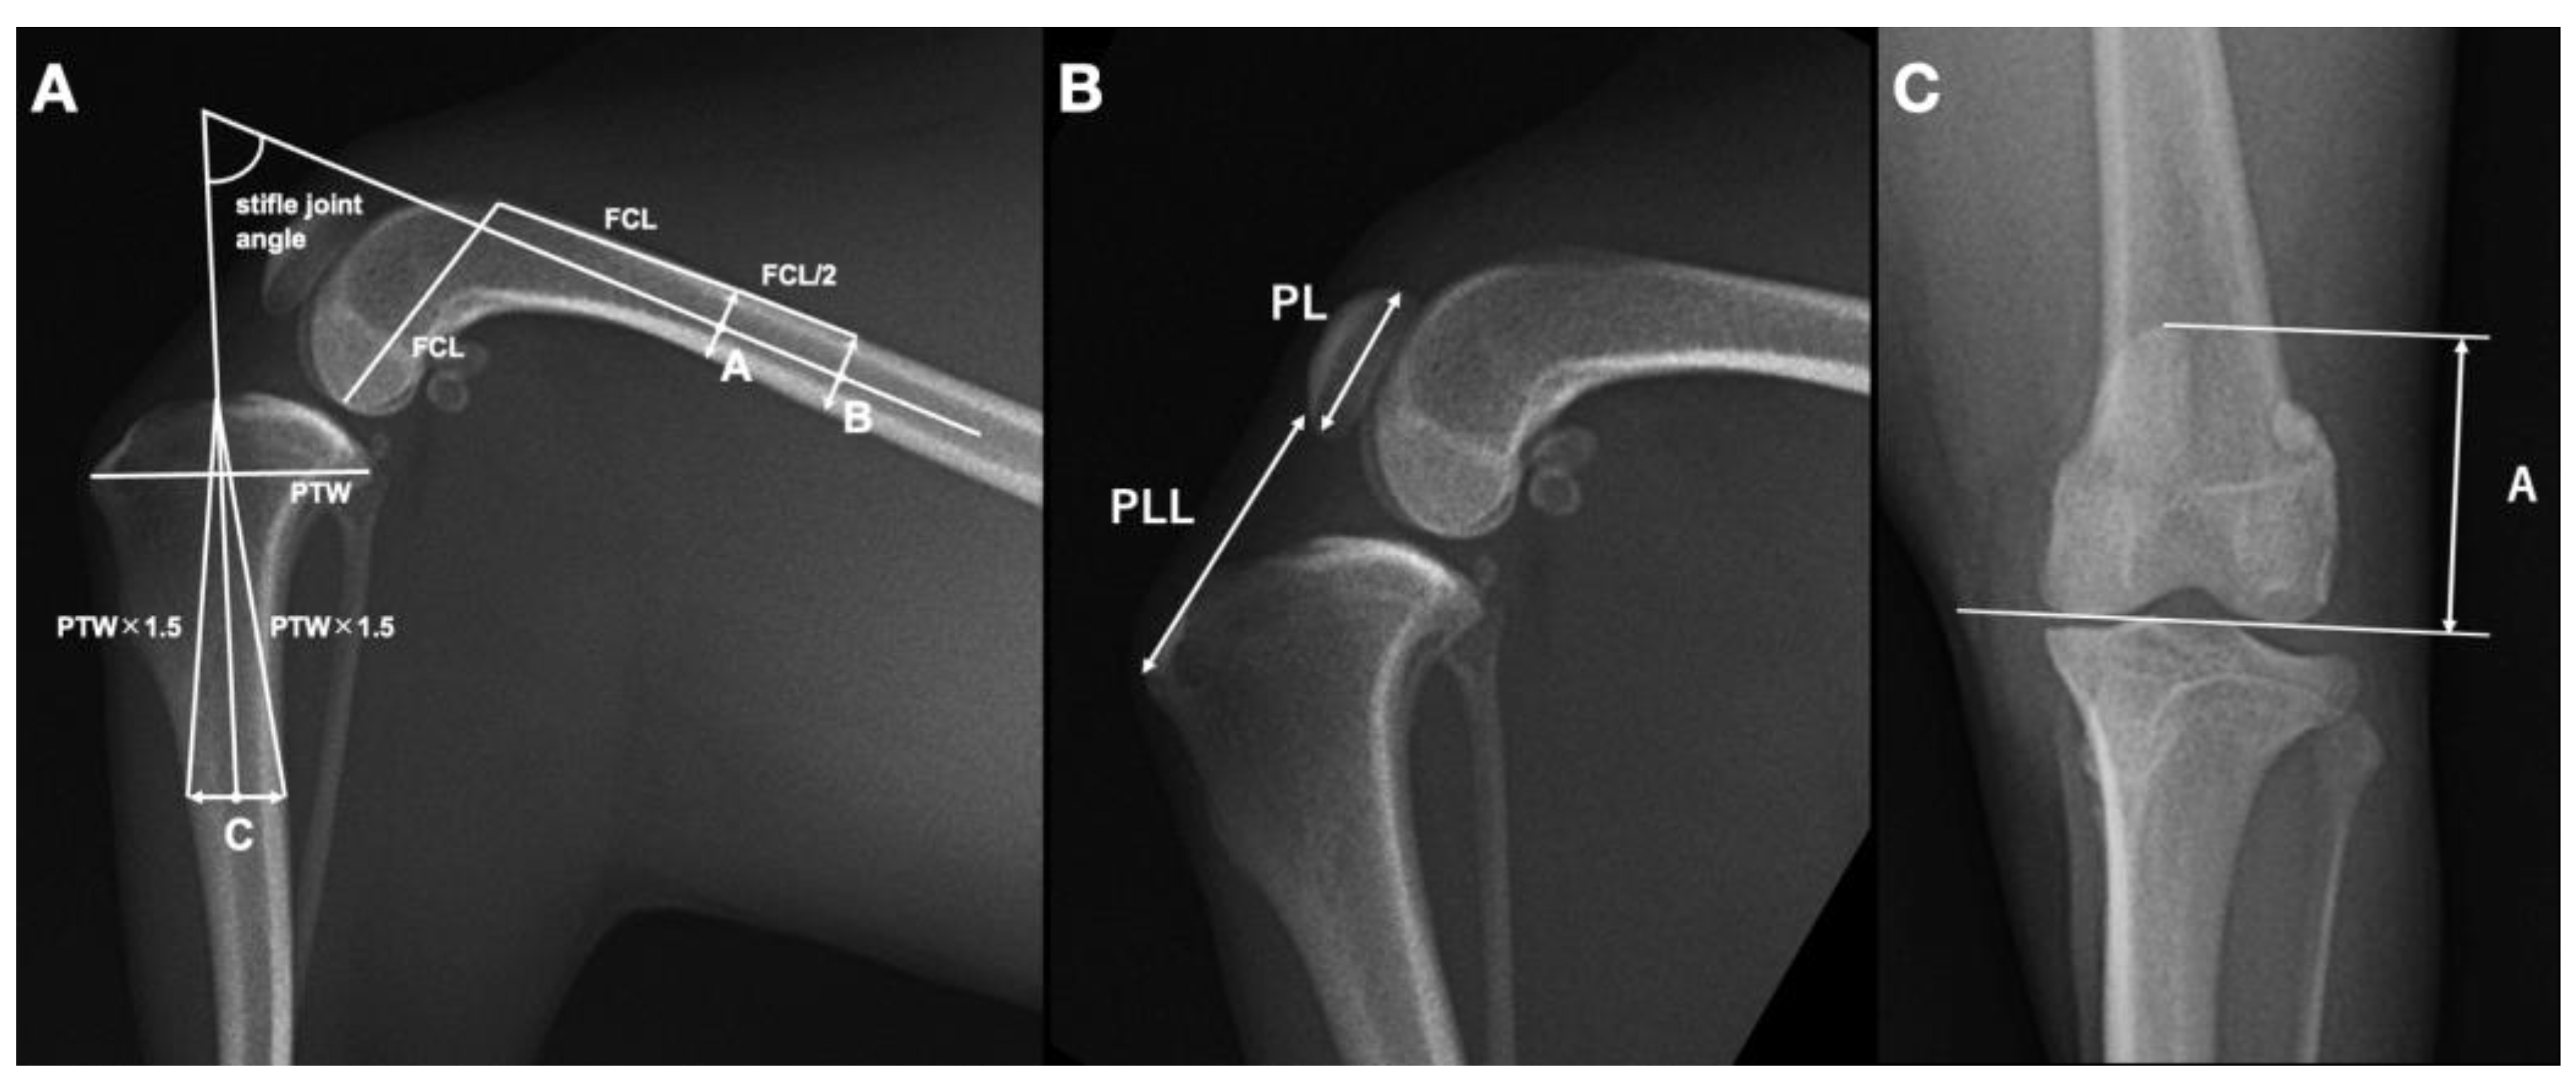

As the PLL is known to be influenced by the stifle joint angle [15], we first measured the stifle joint angle in mediolateral views of the stifle, using a previously described method for small-breed dogs [12]. The stifle angle was defined as the caudal angle formed by the anatomical axes of the distal femur and proximal tibia. The extension of the line connecting the two centers of the femoral width was defined as the distal femoral anatomical axis. The distal femoral width was one femoral condyle length from the proximal end of the trochlea, and the proximal width was half the length of the femoral condyle from the distal one. The proximal tibial anatomical axis was defined as the extension of the line connecting the center of the tibial width, which was 1.5 times the length of the proximal tibial width from the tibial plateau and the cranial notch to the tibial plateau (Figure 1A). Cases with stifle angles outside the range of 70 to 110 degrees [15] were excluded from further analysis.

Next, we measured the PL, PLL, and vertical line (A), according to previously published methods [15]. PL was defined as the distance from the most-proximal to the most-distal aspect of the patella, while PLL was the distance from the most-distal aspect of the patella to the tibial tuberosity (Figure 1B). Care was taken to exclude osteophytes when noted at the distal aspect of the patella. The PLL/PL ratio was then calculated. The distance from the proximal border of the patella to the level of the femoral condylar articular margin (A) was measured on a craniocaudal radiograph (Figure 1C) and indexed to the PL to provide A/PL. The value for PL was measured on the corresponding mediolateral view of the stifle because superimposition over the distal aspect of the patella prevented adequate observation of the distal pole of the patella on caudocranial and craniocaudal projections.

Figure 1. Radiographic assessment of stifle joint angle and proximodistal patella position in a dog using mediolateral (A,B) and craniocaudal (C) stifle radiographs. A: The stifle joint angle (white arc) was measured as the caudal angle between the anatomical axes of the femur and tibia. The femoral anatomical axis was determined by extending the line connecting points A and B, where point A is the midpoint of the femoral width at one femoral condyle length (FCL) proximal to the proximal end of the trochlea, and point B is half the FCL proximal to point A. The tibial anatomical axis was defined by extending the line connecting point C and the notch at the front of the tibial plateau, with point C being the midpoint of the tibial width at a level 1.5 times the length of the proximal tibial width (PTW) distal to the tibial plateau notch. B: The ratio of proximodistal patellar length (PL) to patellar ligament length (PLL) (PL/PLL) was calculated, where PL was the distance from the most-proximal to the most-distal aspect of the patella, and PLL was the distance from the most-distal aspect of the patella to the tibial tuberosity. C: The distance from the proximal border of the patella to the level of the femoral condylar articular margin (A) to PL ratio (A/PL), where PL was measured on the mediolateral view of the stifle.